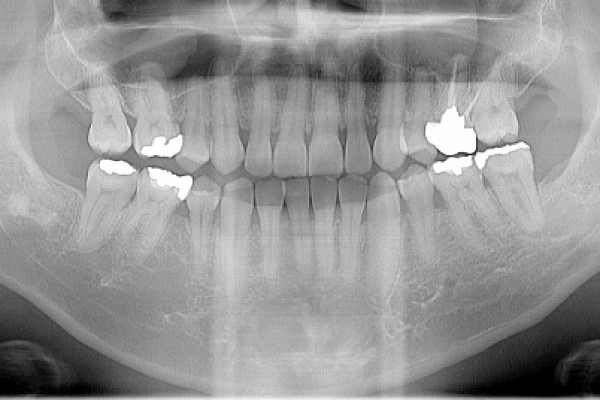

診査・診断

パノラマ、デンタル、CT撮影などの画像診断で治療方針を決めていきます。